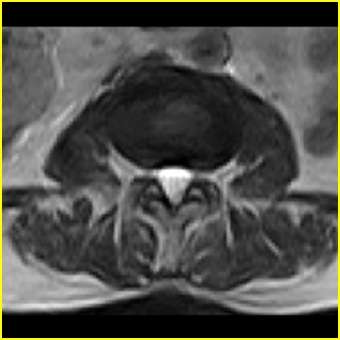

右侧黄韧带肥厚或钙化,压迫马尾神经所致。必要时行ct扫描。

退行性病变:增生、椎间盘变性、膨出[l4-5、l5-s1 椎间盘膨出]

我认为这一层面椎间盘应该合并左外侧型突出。

退行性骨关节病:增生、椎间盘变性、膨出..黄韧带肥厚.

黄韧带肥厚.